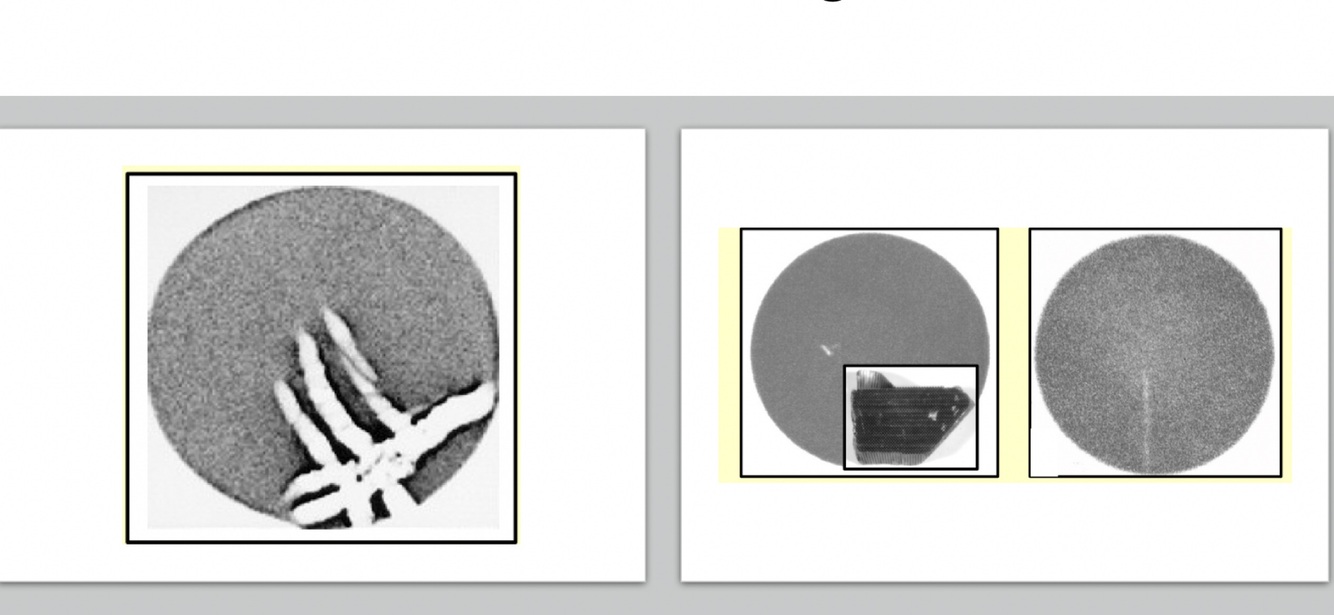

Detector Drop. Wireless flat-panel detectors get dropped. Drops can damage the detector system in several ways through fracturing of the flat-panel detector, through disruption of readout electronics, or through shifting gain and offsets.

Some vendor systems may have integrated diagnostics software to alert the user when detector drops are of sufficient magnitude for a risk to image quality and may provide follow-up instructions for how to respond.

Following instructions that direct a user to seek service or discontinue use of a damaged detector can prevent unnecessary repeated images.

However, because drops occur that can be withstood by detectors without apparent damage and because some systems do not provide user feedback about the effect of a detector drop, the truth of the drop’s effect is sometimes found in an image itself.

How well did you know this?